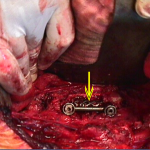

Εικ. 5: Διεγχειρητικές φωτογραφίες

(α) Κύλινδρος τιτανίου (τύπου Harms) που έχει τοποθετηθεί στη θέση του οστικού κενού

(β) Συμπληρωματική σταθεροποίηση της περιοχής με σύστημα σπονδυλοδεσίας M.O.S.S. (βίδες και ράβδους)